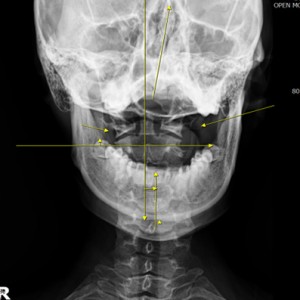

Catch Point 01. 안면비대칭

X·Y·Z축을 바로 잡는 안면비대칭 3D 입체교정

미간, 콧대, 턱, 목선 맞추기

눈썹 높이 수평

입꼬리 수평

두상 위치 균형

어깨 비대칭 개선

안면 두개골 엑스레이 검사

Submento Vertex View 포함

안면 균형검사

턱의 다양한 각도 사진 촬영